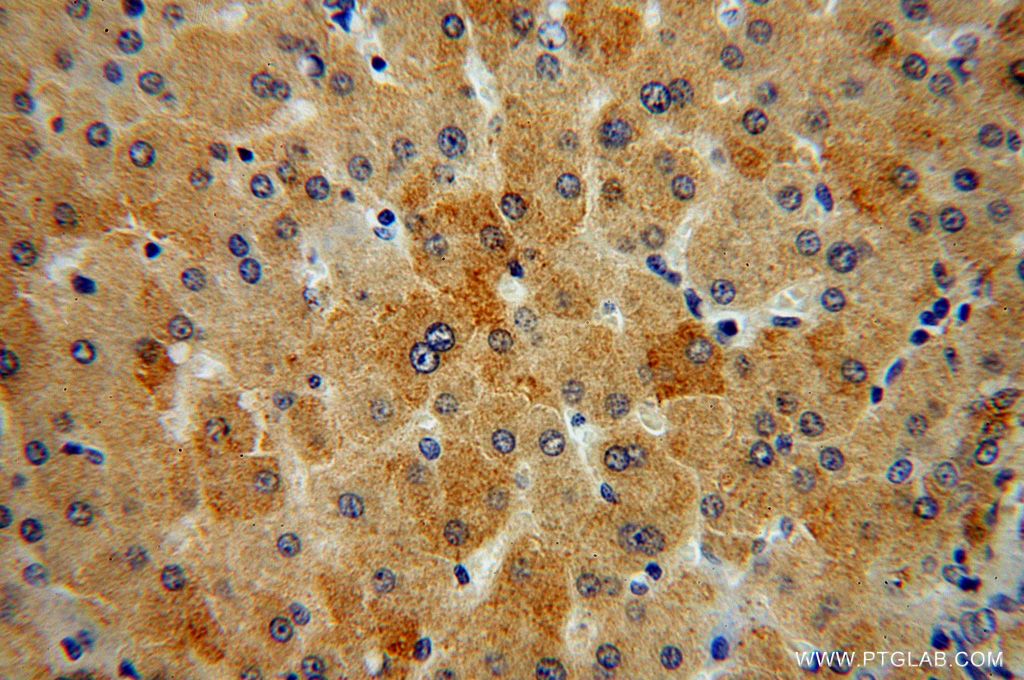

使用范围: WB,ELISA,IHC-P,IHC-F,IF